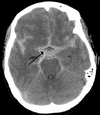

Extradural haemorrhage

This is a haemorrhage between the skull and dura mater of the meninges.

Commonly caused by trauma to the pterion, with subsequent tearing of the middle meningeal artery,

patients present with acute severe headache, contralateral hemiplegia, and a rapid deterioration in GCS following a lucid period.

On CT, a biconvex hematoma is diagnostic.

This occurs as the haemorrhage stops expanding at the sutures of the skull, where the dura meets the skull, causing the haemorrhage to expand towards the brain.

Neurosurgical

intervention is usually needed.

Haematoma expansion limited by sutures of the skull so expands towards the brain giving characteristic biconvex hyper dense area

Extradural haemorrhage is usually caused by rupture of the middle meningeal artery in the temporo-parietal region. It can be associated with a fracture of the temporal bone. It occurs between the skull and dura mater. On a CT scan they have a bi-convex shape and are limited by the cranial sutures (they can’t cross over the sutures).